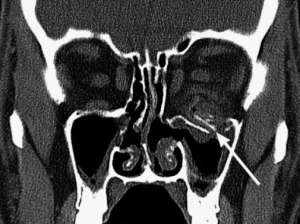

Рентгенологическое исследование данной области позволило оценить нарушение целостности костей по следующим признакам: видимая линия перелома, нарушение гладкости контура кости и расхождение отломков костей в скулолобной (п=53; 49,1%), подглазничной (п=54; 50%), скулоальвеолярной областях (п=50; 46,3%). Увеличение объёма травмированной орбиты отметили в 32 случаях (29,6%). Также встречались косвенные признаки травматических повреждений средней зоны лица: затемнение верхнечелюстного синуса на стороне травматического воздействия (п=58; 53,7%) и в области мягких тканей средней зоны лица (п=56; 51,9%). Признаки инородных тел средней зоны лица и орбиты отметили у 10 пациентов (9,3%).

Детальную информацию о состоянии мягких тканей орбиты при использовании рентгенологического метода получить не удалось (рис. 2).